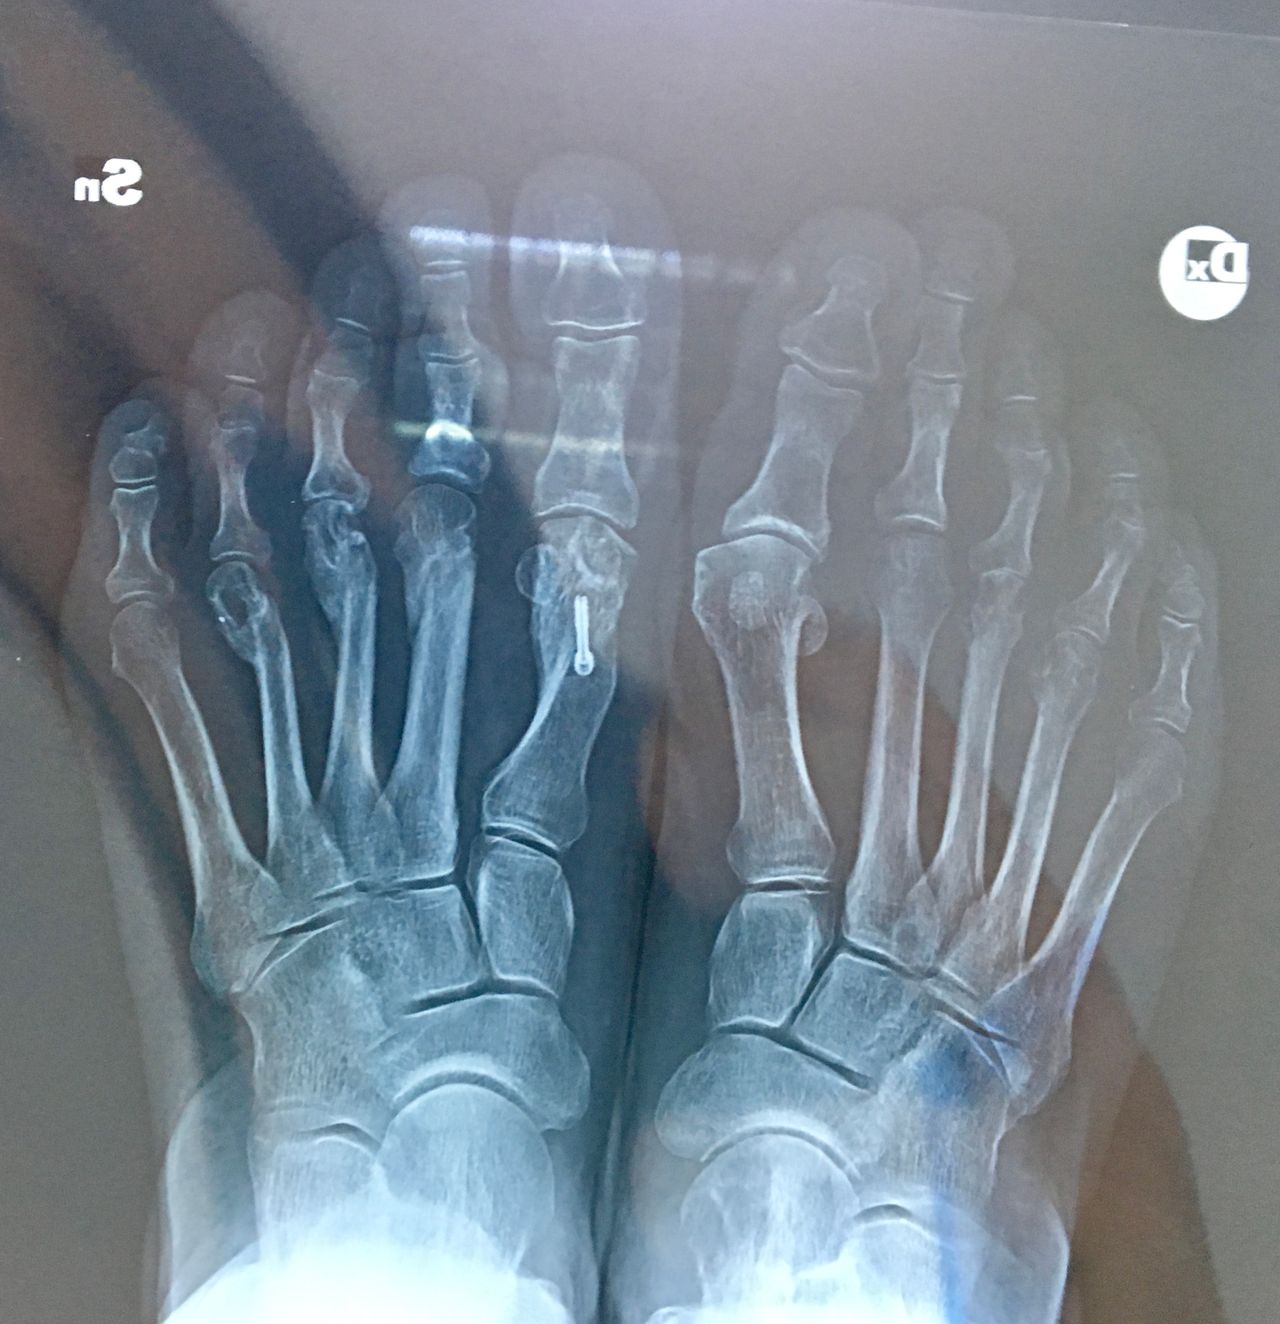

La chirurgia del piede

Alluce valgo

• Chirurgia del piede